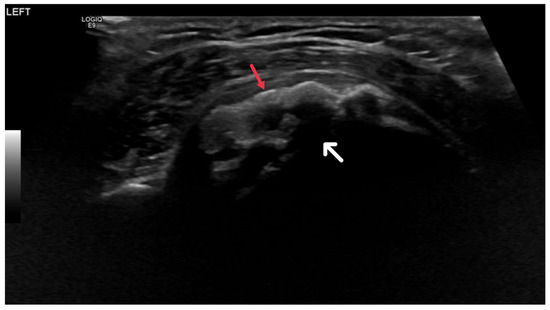

Ultrasound utilizes high-frequency sound waves to generate images of the body’s internal structures. For HADD diagnosis, ultrasound is critical in identifying the size, shape, and location of hydroxyapatite deposits, which manifest as hyperechoic foci within soft tissues due to their high reflectivity [29].

These deposits may correspond to acoustic shadowing, a phenomenon where ultrasound waves are obstructed by the deposits, leading to an image shadow (Figure 7). This feature is of diagnostic value, as it differentiates hydroxyapatite deposits from other soft tissue abnormalities [30]. Furthermore, ultrasound can detect inflammation and tendon damage through increased echogenicity of the surrounding tissues and alterations in tendon size, shape, and echotexture [31].

Figure 7. Ultrasound image showing calcific focus at the supraspinatus tendon insertion (red arrow) with posterior acoustic shadowing (white arrow).